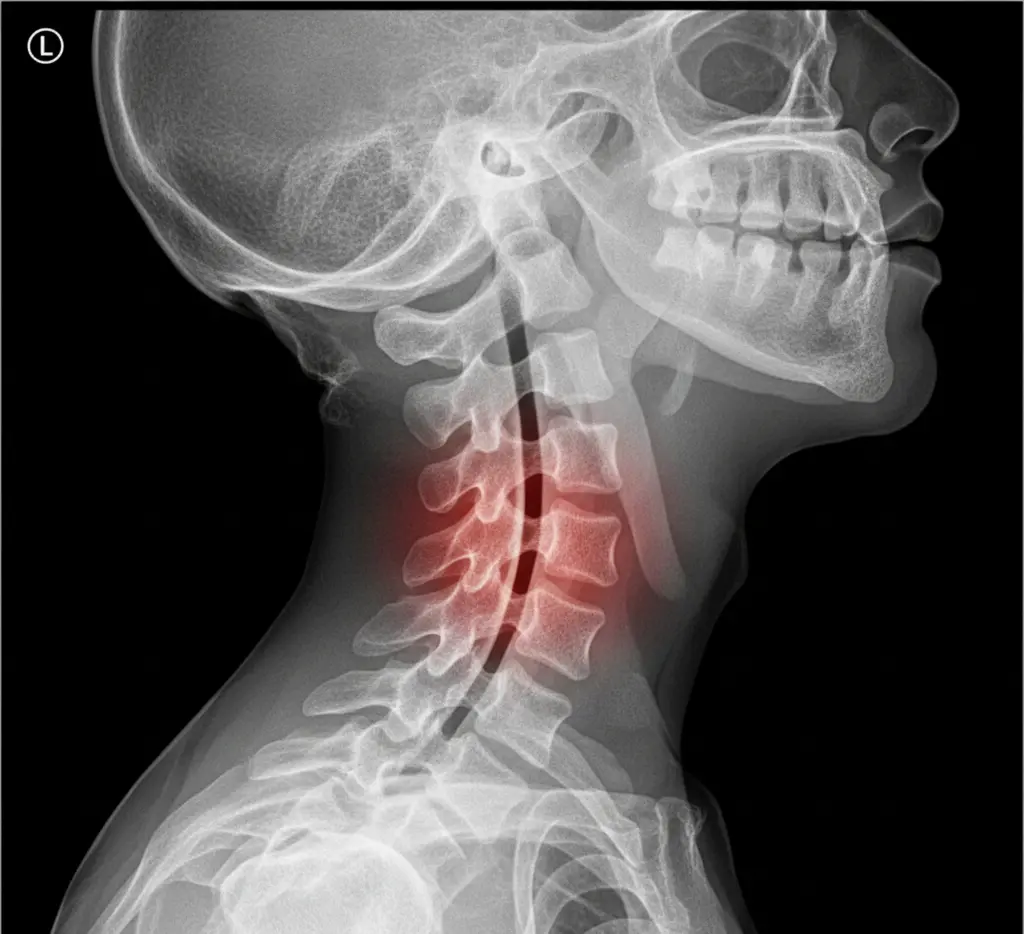

What is Cervical Spinal Stenosis?

Cervical spinal stenosis is a condition where the spinal canal in the neck narrows, potentially compressing the spinal cord and nerve roots. This narrowing can occur in the cervical spine’s bony openings (foramina), reducing space for nerves and/or the spinal cord.

Cervical Spine Stenosis

In the cervical spine, narrowing can cause different symptoms based on whether the spinal cord or nerve roots are compressed: